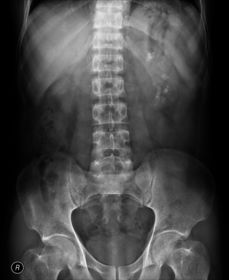

Glomerulonephritis (left) inflammatory disease of the capillary loops of the renal glomeruli (within nephrons) AKA bright disease Commonly developed after streptococcal infection due to antigen-antibody deposited in glomerulus Commonly causes underdeveloped kidneys Characterized by hypertension Symptoms: nausea, malaise, and joint pain Lab test show: increase in albumin, BUN, and creatinine CXR has pulmonary infiltrates Radiographic Appearance: can lead to renal failure, if chronic it leads to fibrosis, leading to the kidney shrinkage, scarring, and shrinkage but initially the kidneys are enlarged due to inflammation